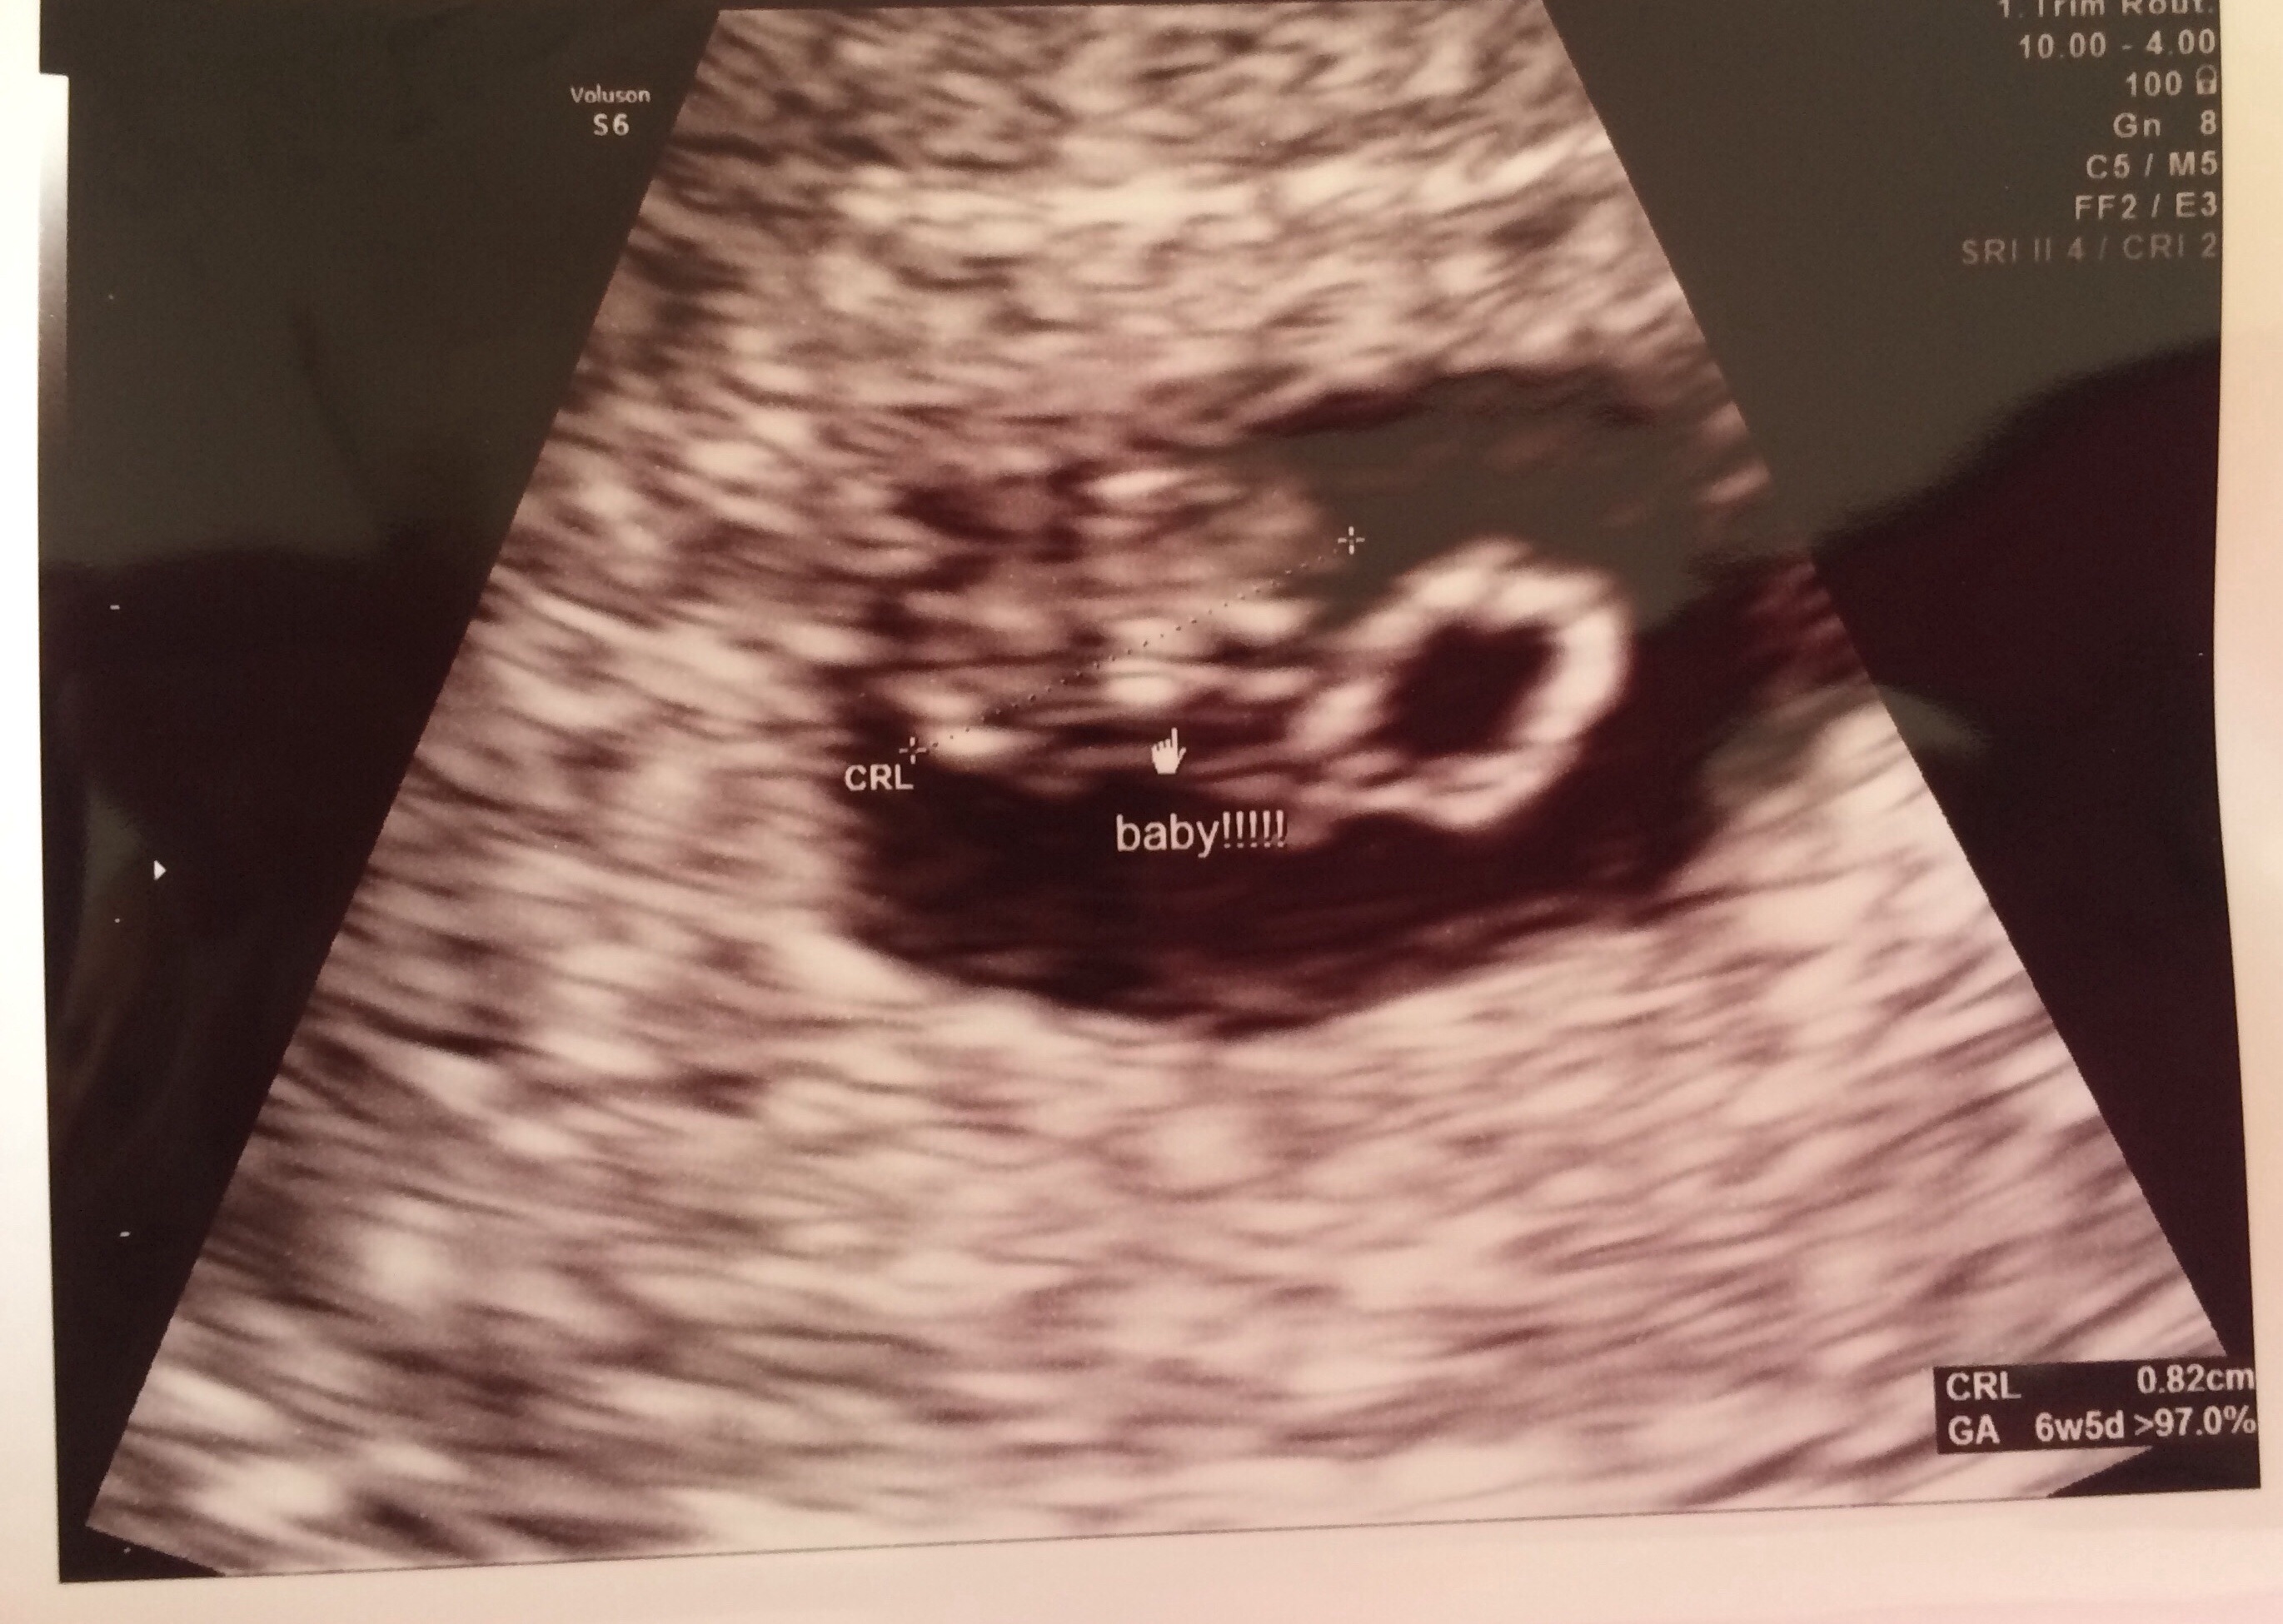

• Here's mine I thought I was 7 weeks but I was 6 weeks 5 days